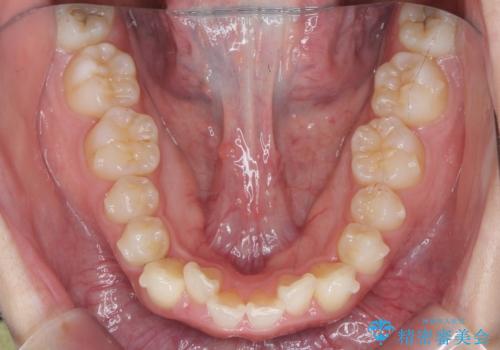

- ねじれの目立つ前歯の見た目を改善したいと矯正治療を希望され来院されました。

がたつきの改善をマウスピース矯正インビザラインで行っていきます。

ガタつきの改善はもちろん、歯列全体のアーチも放物線状にきれいに排列し審美性を向上させることができました。